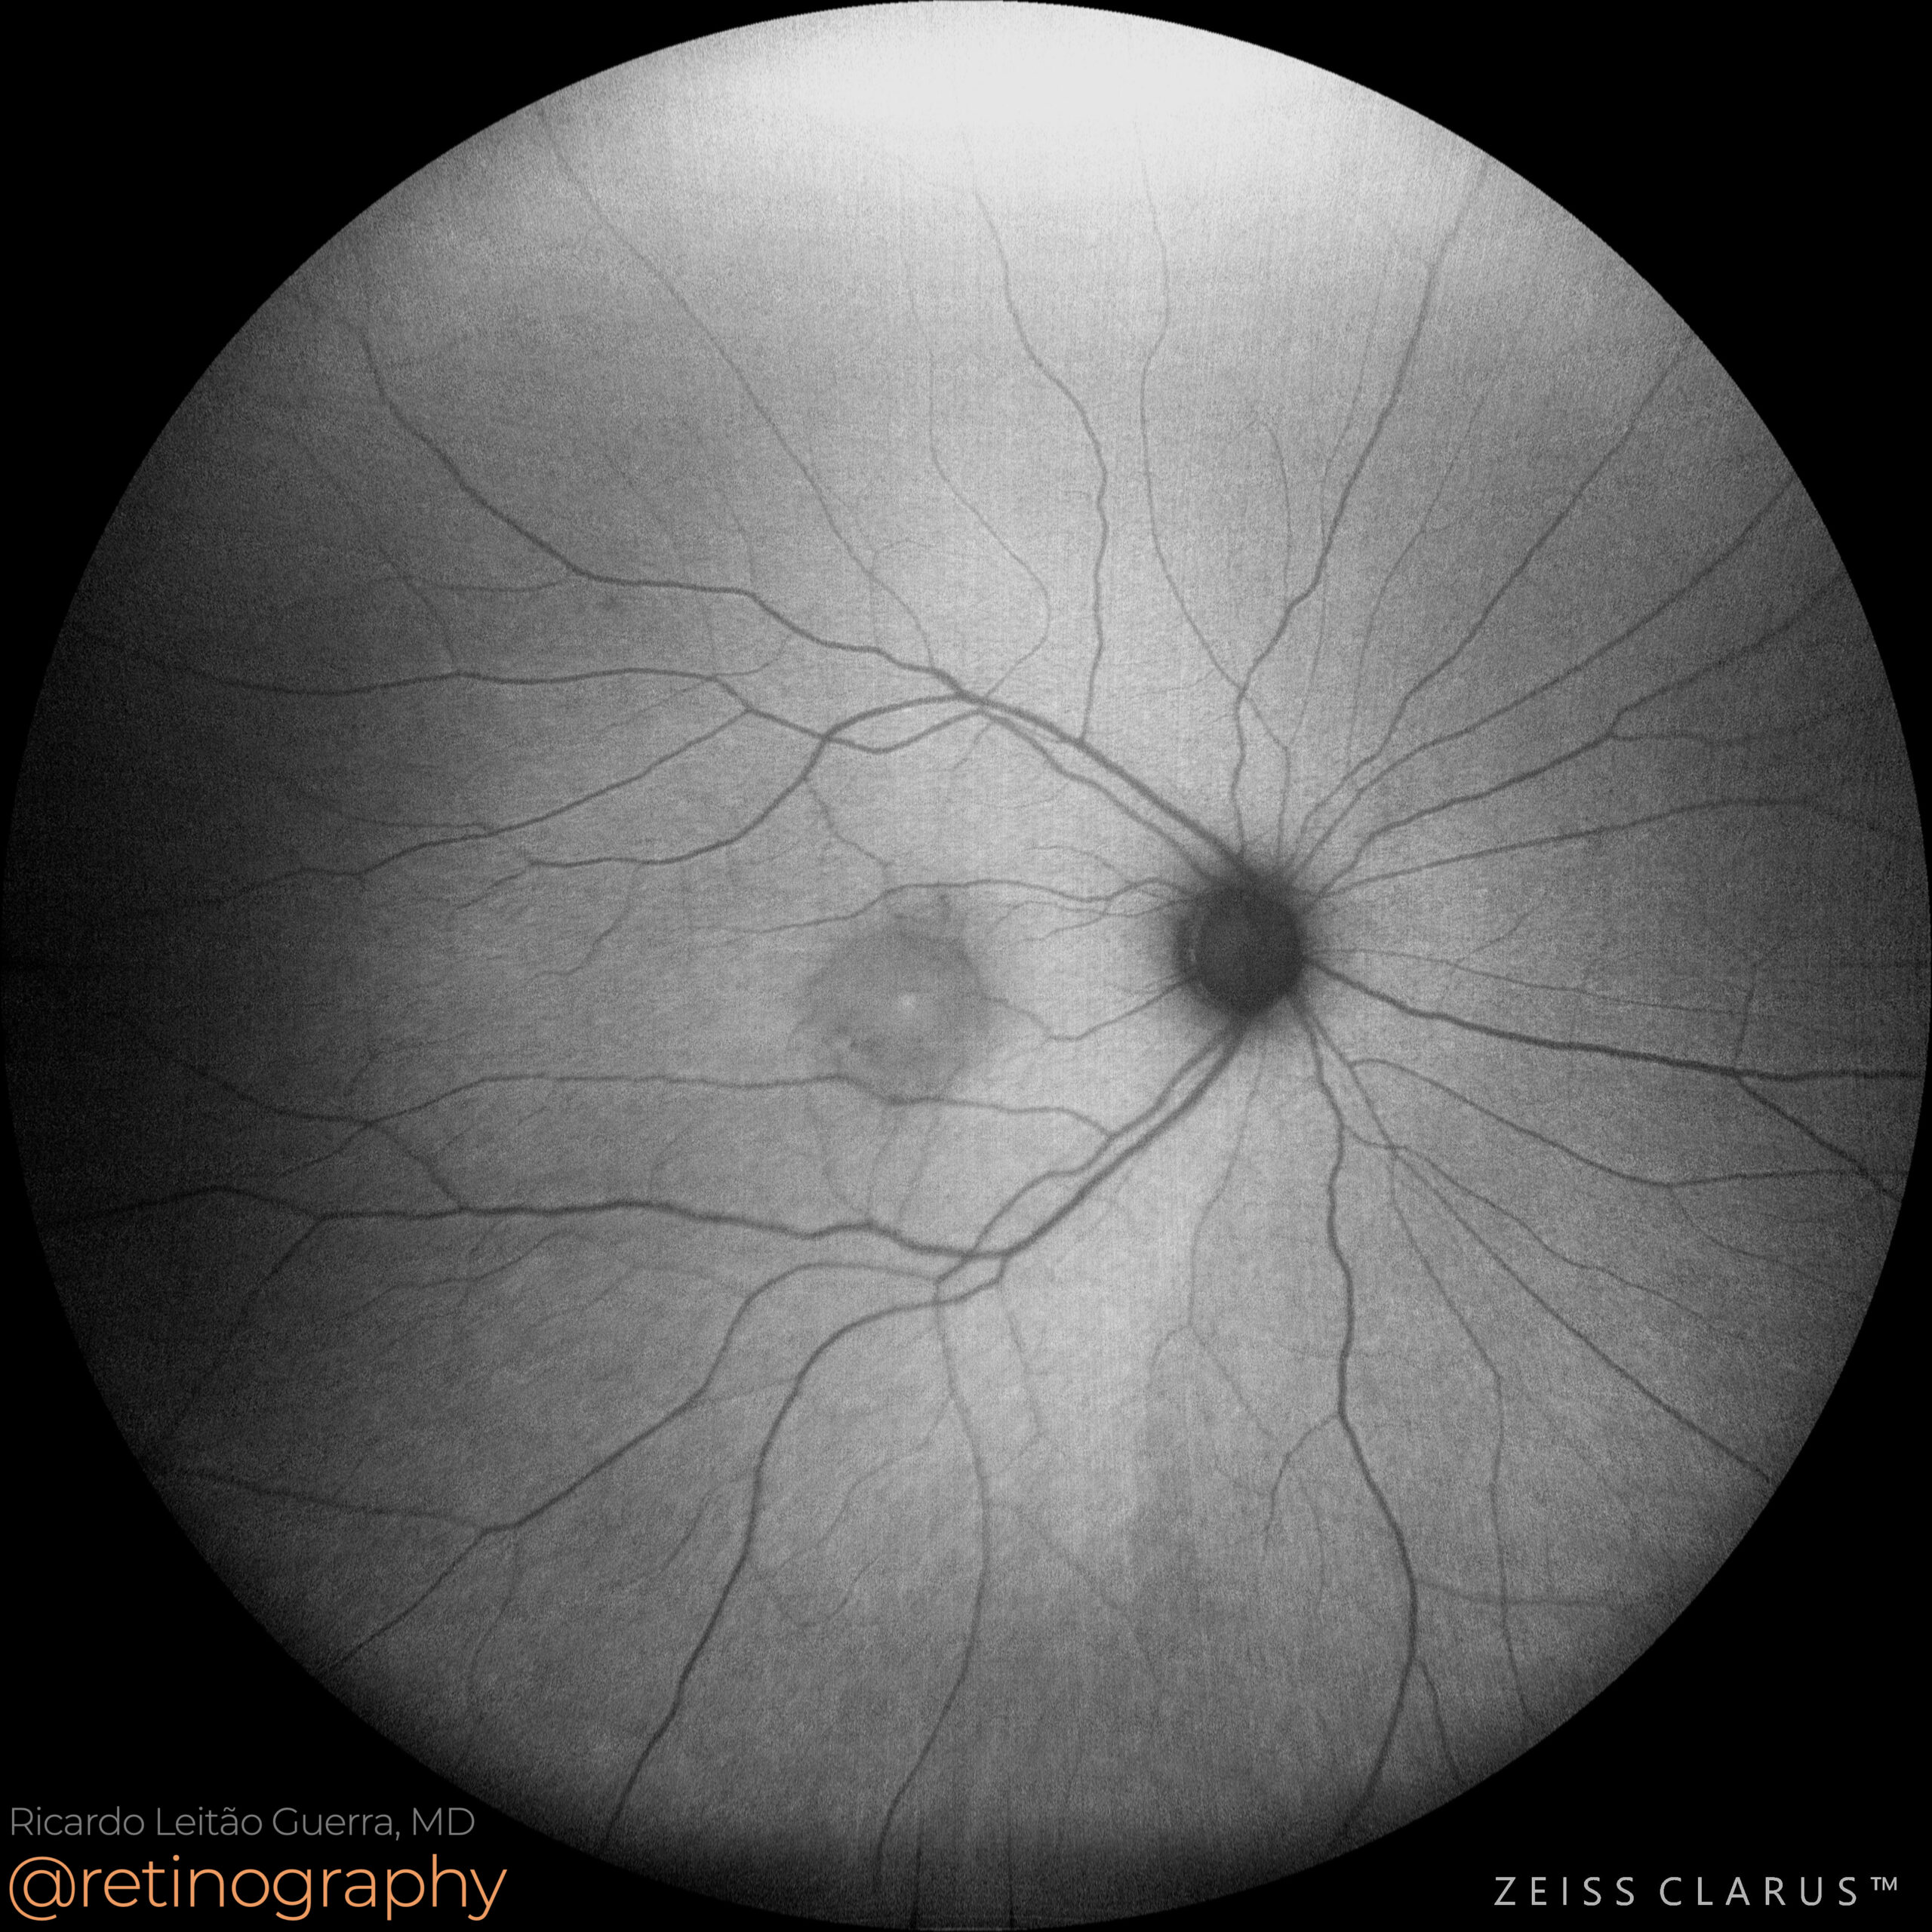

Central serous chorioretinopathy

42yo

42yo